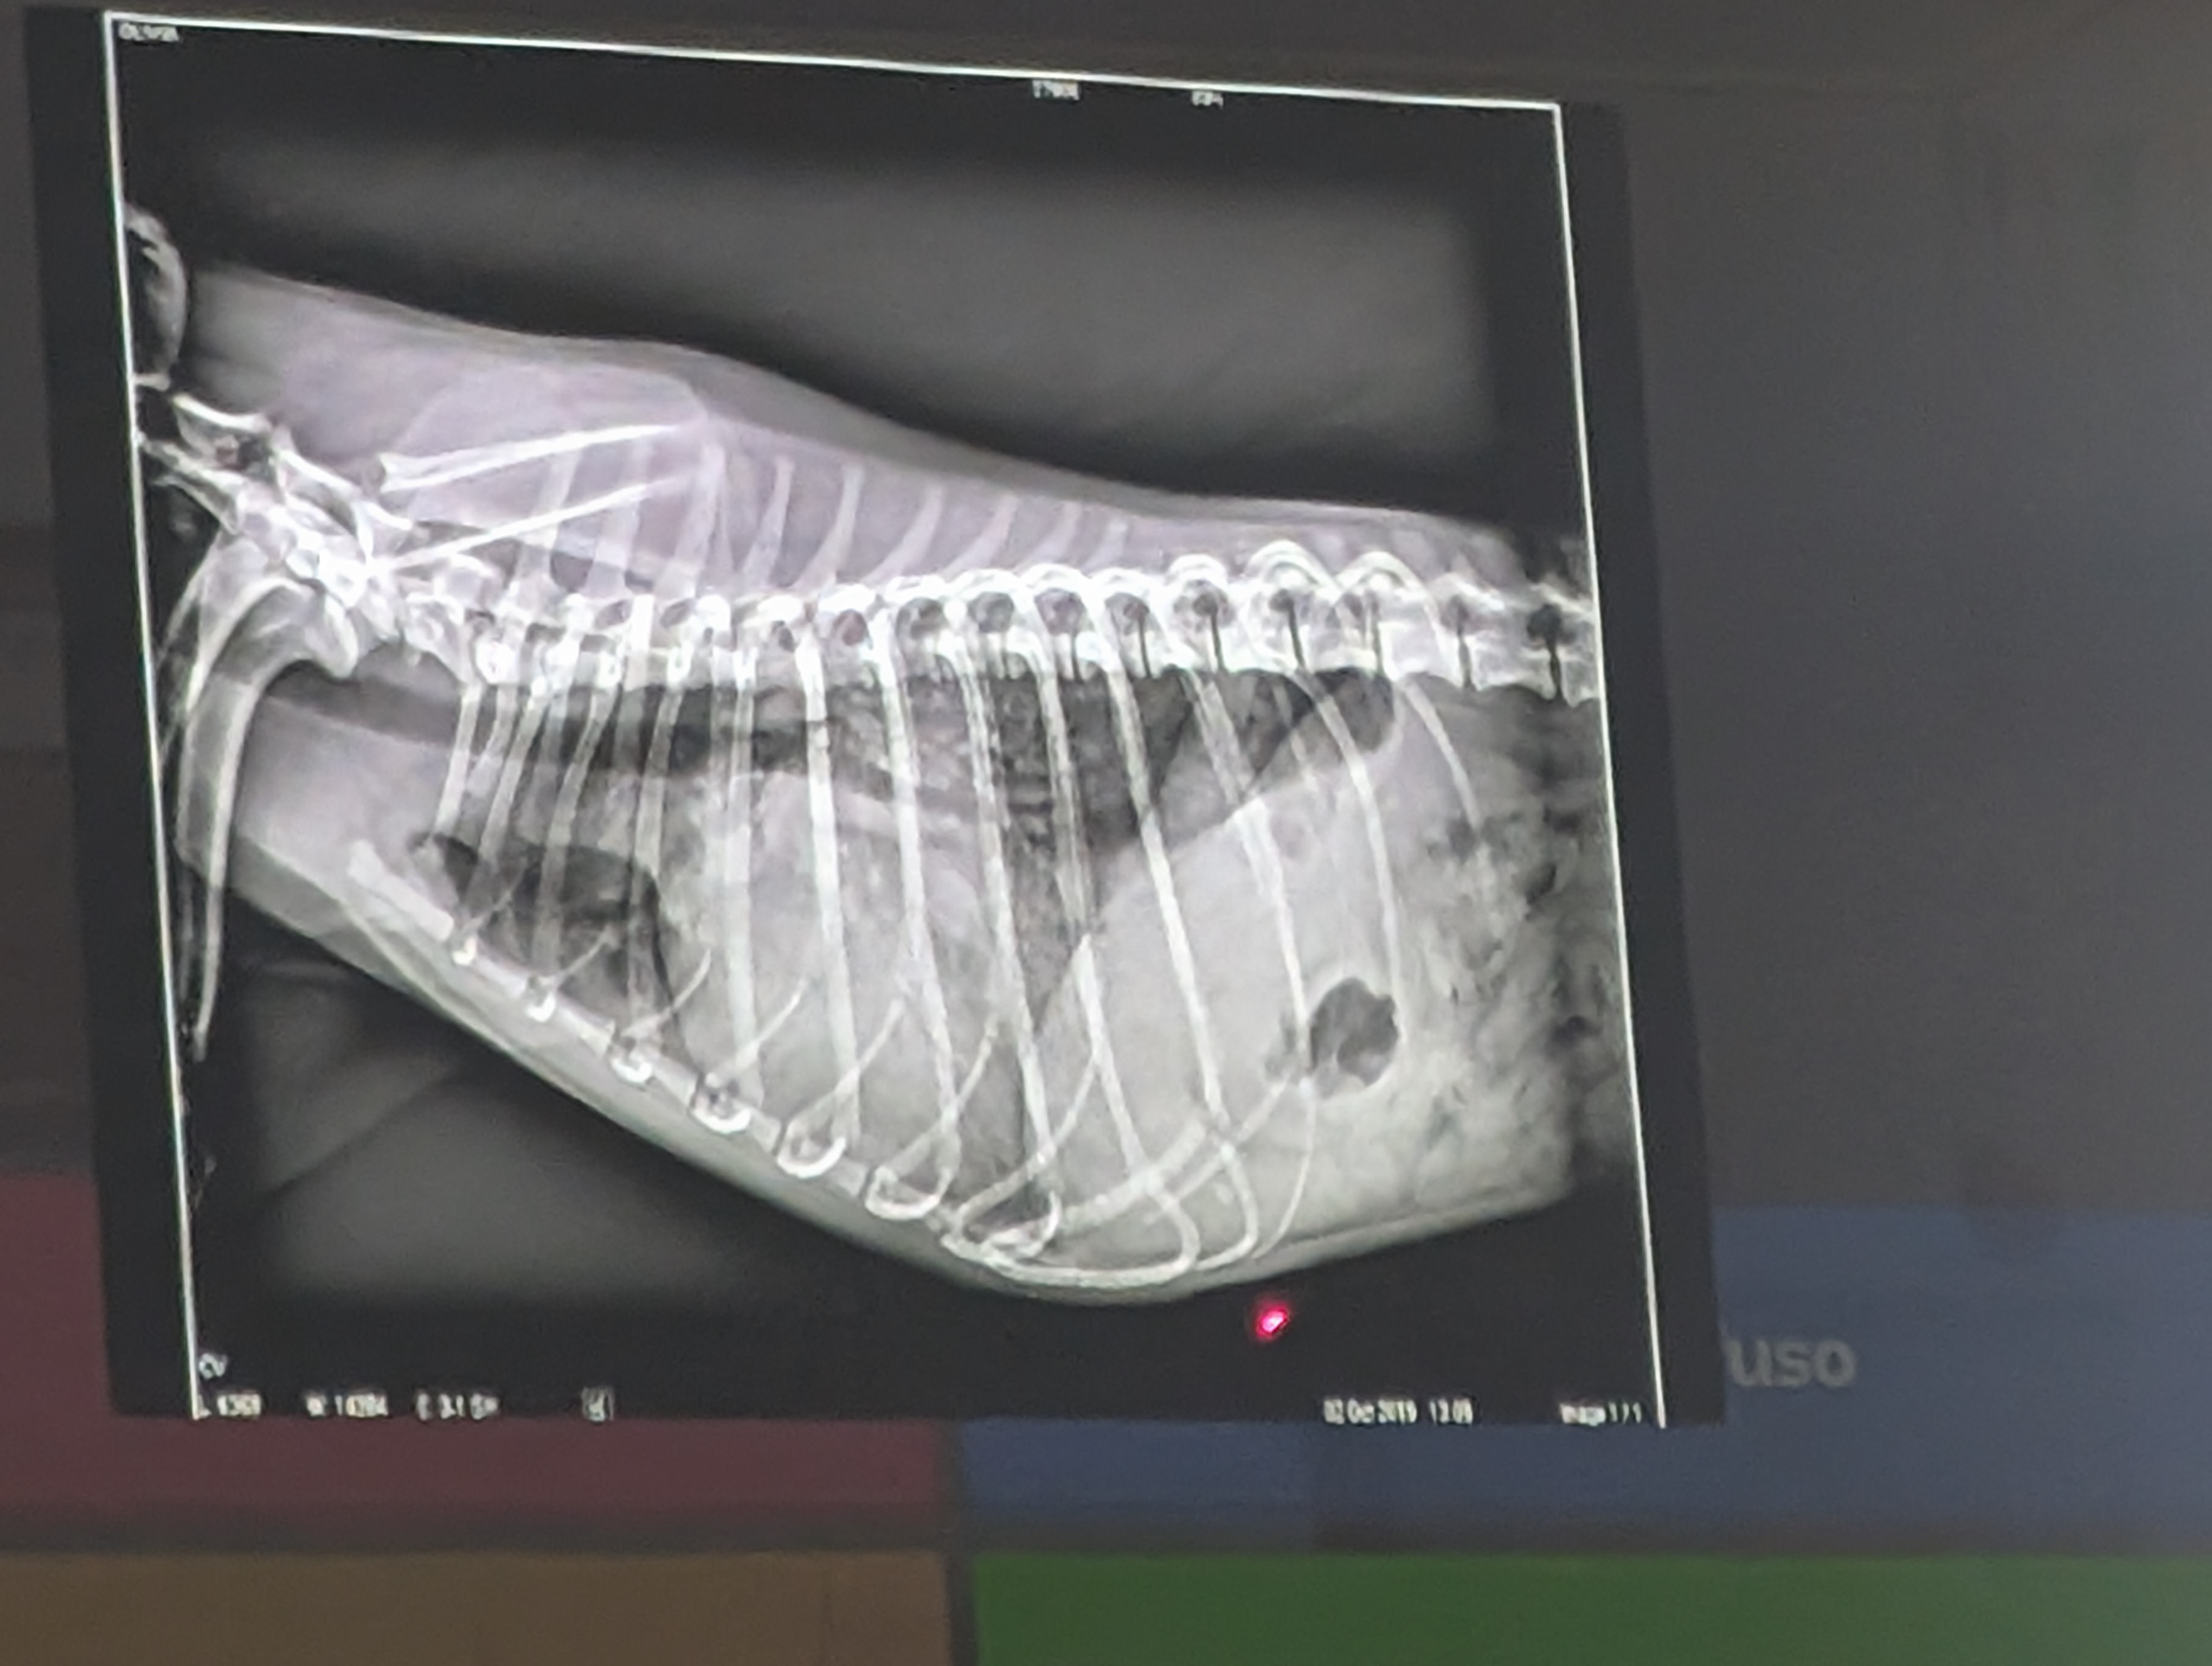

Preguna 2 - Multiple respuesta

- Se trata de un abdomen de perro

- Dilatacion gastrica

- Cuerpo extraño en el estomago (Linea radiopaca en el piloro)

- Eje gastrico alterado.

- Cumple dos criterios de hepatomegalia. (El higado ocupa mas parte, avanzando mas costillas, desplaza al estomago)